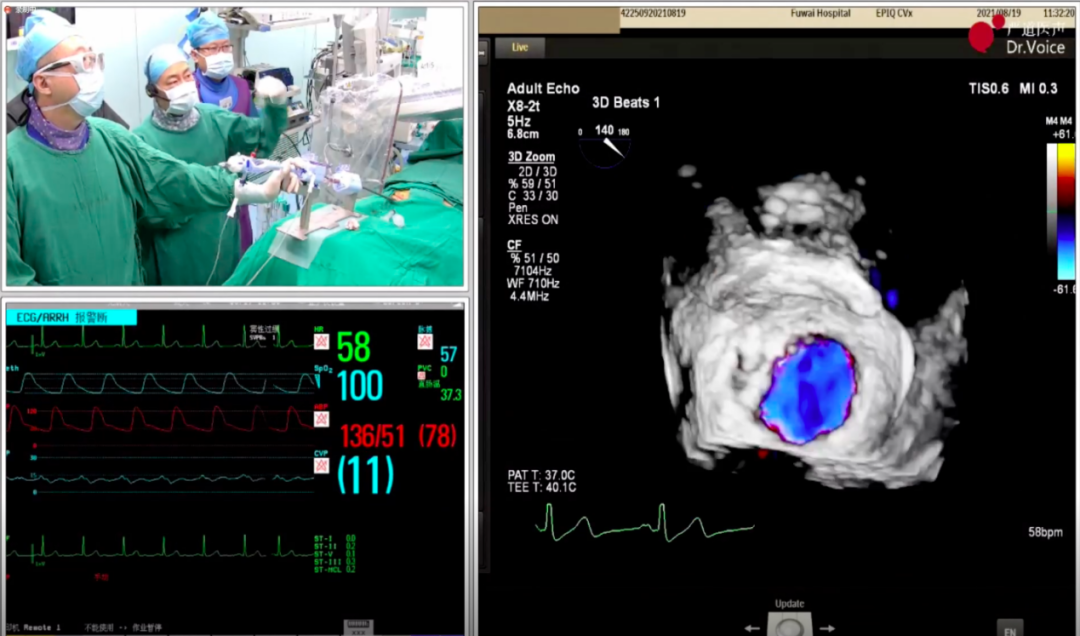

2021年8月19日,在国家结构性心脏病介入质控中心瓣膜介入技术培训会上,中国医学科学院阜外医院结构性心脏病中心潘湘斌教授团队借助经导管二尖瓣夹及可操控导引导管MitraClip®,顺利完成1例高难度二尖瓣交界病变修复手术,并向与会嘉宾直观展示和总结了MitraClip®手术方案决策和术中操作技巧。

手术过程

1、手术团队使用MitraClip®独特的三层双调弯导管,经股静脉穿刺,在食道超声引导下完成房间隔穿刺。穿刺后将导管送入左心房,靠近二尖瓣目标位置。术中TEE三维超声可明确显示瓣膜脱垂区域,脱垂区域主要位于二尖瓣前叶A1区及前交界,且面积较大,显著增加手术难度。

三维超声显示瓣膜脱垂区域